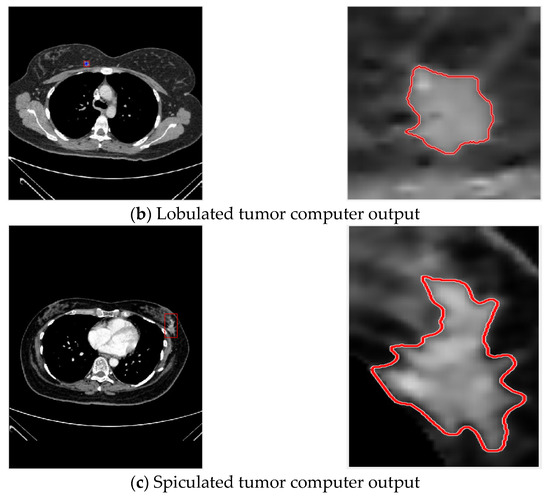

In this study, breast tumor images were divided into three types according to features of their margins [29,30,31], namely, circumscribed tumors, lobulated tumors, and spiculated tumors, as shown in the Figure 1.

Then ACWE is used for tumor contour extraction, with circled results shown in Figure 7.

Figure 7.

Contour selection of tumors.

3.3.2. Excessive Centroid Point Movement—Breast Tumor Circle Selection

Spiculated tumors are tumors with large changes in their centroid positions, but the various parts of the tumor ROI can be extracted and magnified by bilinear interpolation in the same way as with the aforementioned circumscribed and lobulated tumors.

The result of convergence with the region-based active contour ACWE method is shown in Figure 8.

Figure 8.

ACWE contour circle selection results for spiculated tumor.